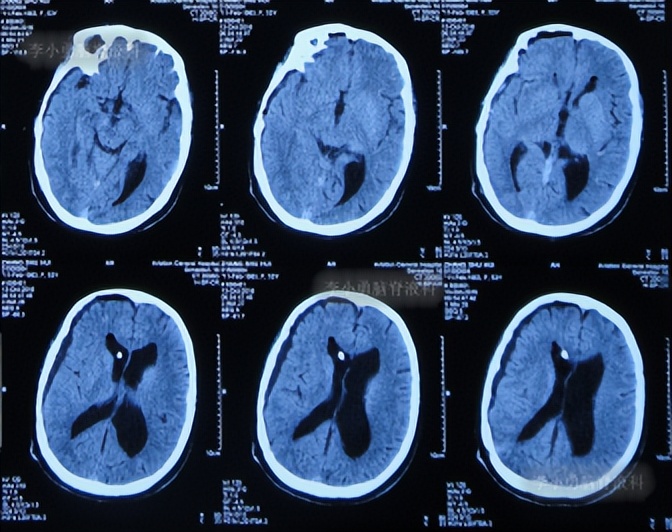

第2次出院后4月余即2016年6月7日,因第3次“发热”就诊当地某医院中医门诊,经中医治疗近两月时间。于2016年6月21日复查头颅CT:幕上脑室仍扩张( 图-7 )。治疗期间发热曾缓解,但之后发热仍反复。

图-7: 2016年6月21日头颅CT

住院后3天即2016年8月19日,查头颅CT:幕上脑室扩张( 图-9 )。

图-9: 2016年8月19日头颅CT

第3次出院后21天即2016年9月23日,复查头颅CT:幕上脑室仍扩张( 图-10 )。

图-10: 2016年9月23日头颅CT

当天头颅CT:脑积水右侧侧脑室分流术后,脑室扩张并间质性脑水肿( 图-12 )。

图-12: 2016年10月7日头颅CT